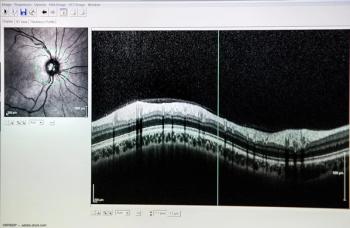

Amitha Domalpally, MD, PhD, discusses how disorganization of retinal inner layers affects OCT outcomes in cases of uveitic macular edema.

The collaboration will bring automated, AI-powered OCT segmentation to MICRON Software Suite.

The program will use OCT images to identify and monitor AMD in its early stages.